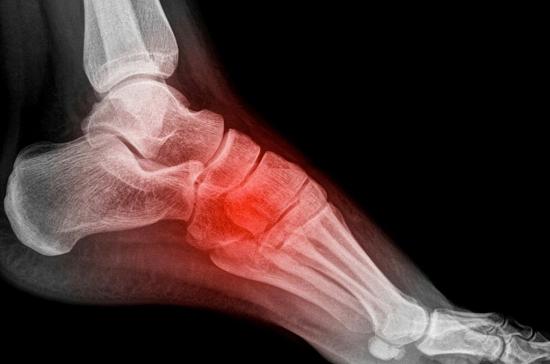

При фасциите воспаляется подошвенная фасция, которая соединяет пяточную кость с фалангами пальцев ног. Воспалительный процесс развивается из-за постоянного натяжения связок, в результате чего в фасции происходят микроразрывы, а пяточная кость повреждается. Разрывы постепенно увеличиваются, окружающие ткани отекают, и возникает боль в ступне.

Подошвенный фасциит охватывает, как правило, обе конечности, но возможно и одностороннее поражение. Наиболее частым осложнением является пяточная шпора – костный нарост на пяточной кости, состоящий из солей кальция. Для лечения плантарного фасциита используются нестероидные противовоспалительные препараты, массаж, лечебная гимнастика. Обязательным условием является ношение ортопедической обуви либо специальных вкладышей – стелек и супинаторов.

Клиническая картина пяточного артроза напоминает проявления пяточной шпоры – боль возникает в подошве, ближе к пятке, ограничивается подвижность голеностопа, кожа над суставом становится горячей. По мере развития болезни появляются наросты на пяточной кости (остеофиты), при движениях слышится хруст из-за кальциевых отложений, сустав реагирует болью на изменение погодных условий.

Клиническая симптоматика артроза сильно напоминает пяточную шпору, при которой боль появляется в подошве, сбоку (ближе к пятке), ограничивая двигательную активность голеностопного сустава. По мере усиления симптоматики возможно образование остеофитов, хруст при движении и метеочувствительность.